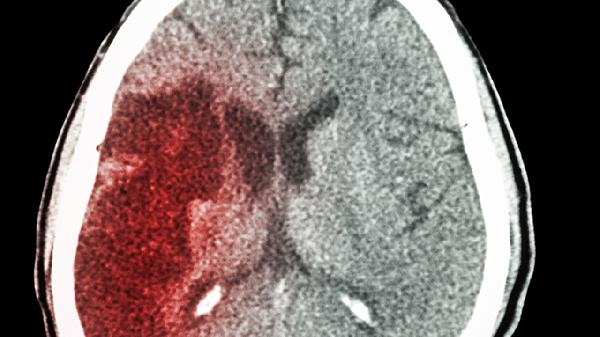

头颅CT平扫可明确原出血灶吸收情况及是否存在脑软化灶,增强CT能鉴别术后粘连与复发血肿。优先选择无创的磁共振SWI序列检测含铁血黄素沉积,DWI序列有助于发现新发隐匿性梗死灶。血管成像需关注动脉瘤术后金属夹伪影干扰。